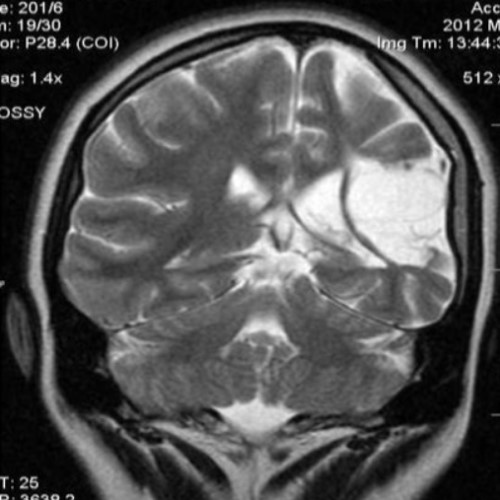

Демиелинизирующие заболевания мозга: МРТ изображения